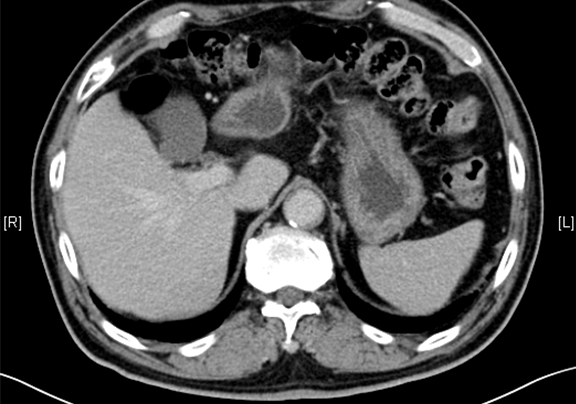

术前CT检查:

动脉期

静脉期

平衡期